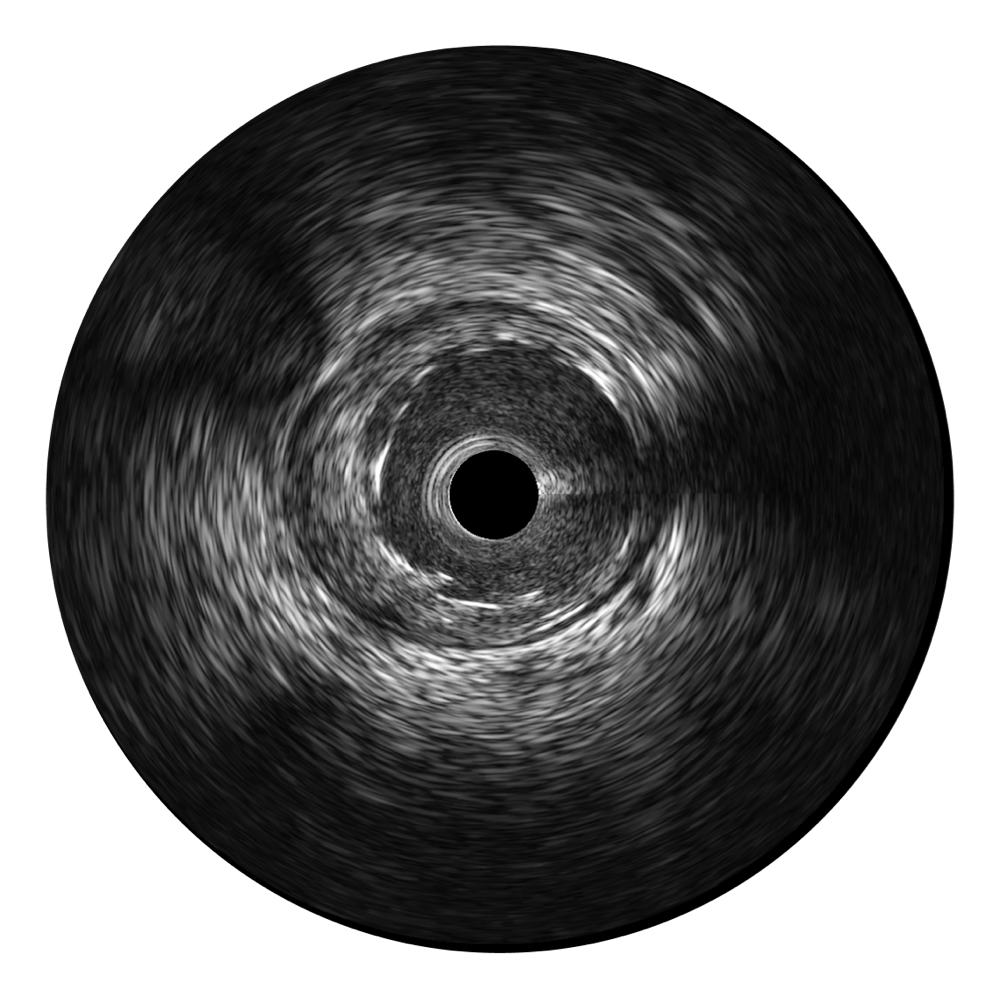

• 传统IVUS图像

对比传统IVUS导管成像,玖鼎集团宽频IVUS图像的近场支架梁显影更细腻,远场中膜外血管仍清晰可辨,兼顾远中近,兼顾分辨力与穿透深度